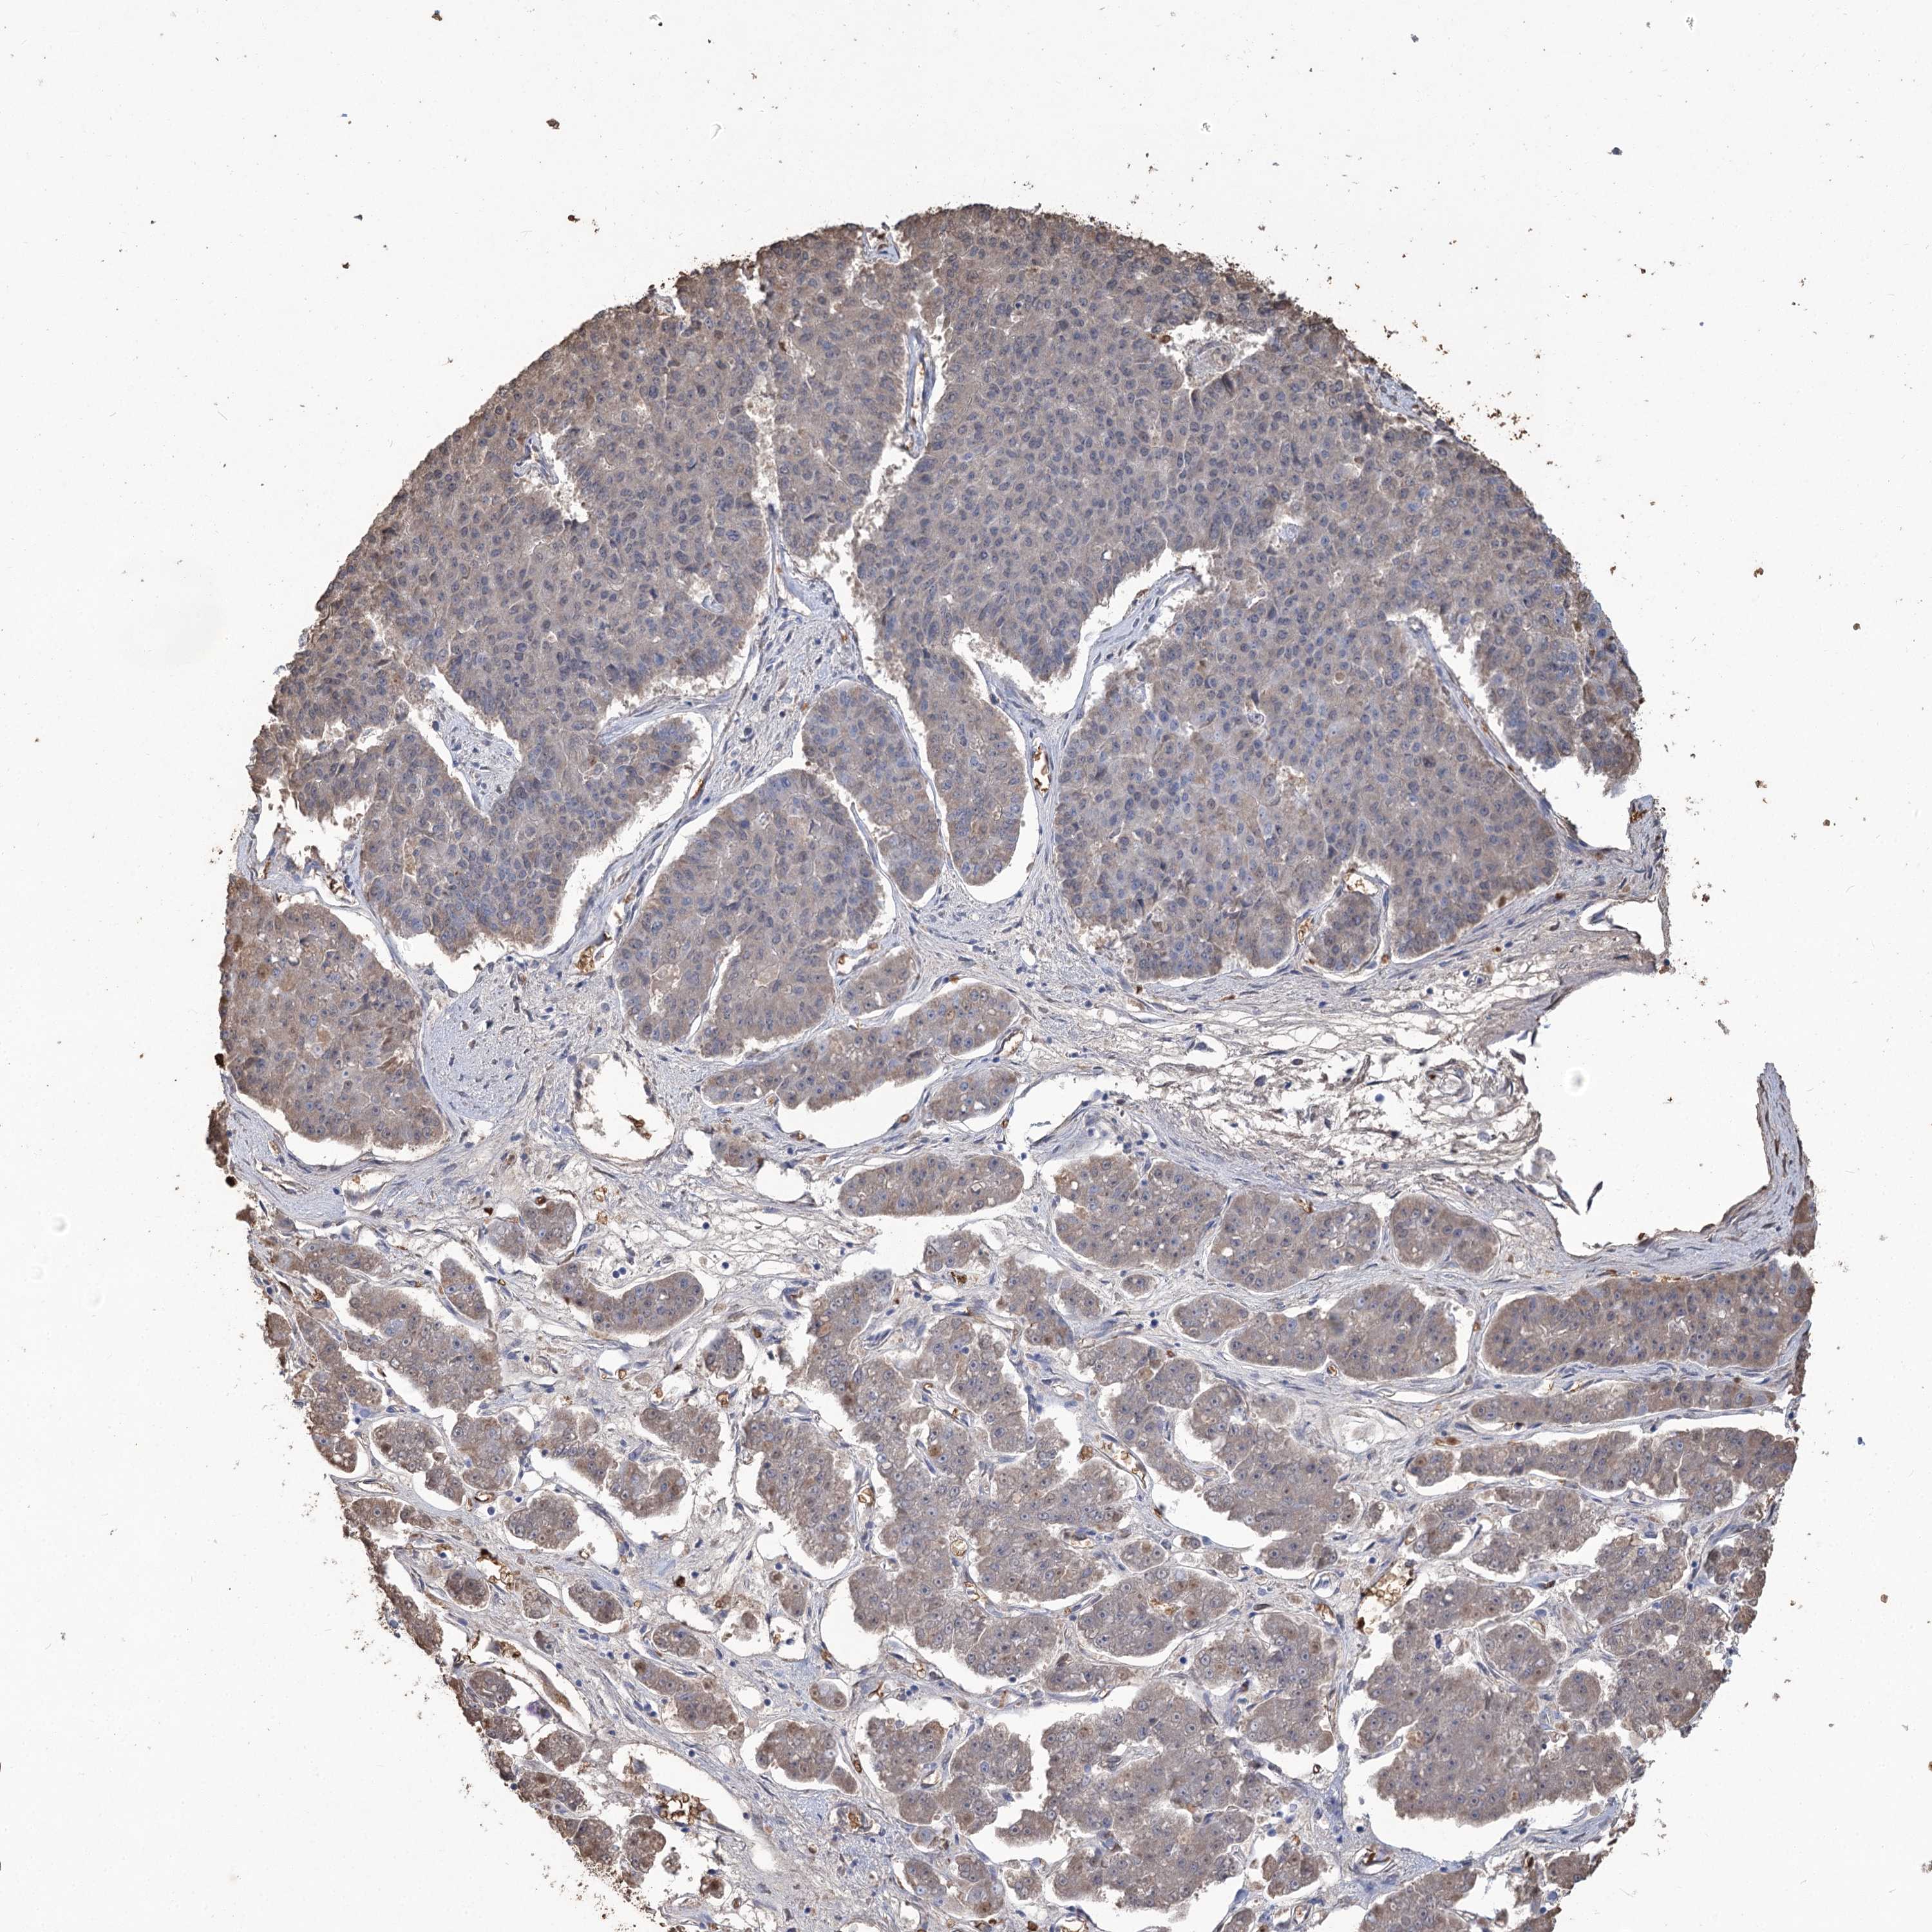

PANCREATIC CANCER - Protein expressioni

A mouse-over function shows sample information and annotation data. Click on an image to view it in a full screen mode. Samples can be filtered based on level of antibody staining by selecting one or several of the following categories: high, medium, low and not detected. The assay and annotation is described here.

Note that samples used for immunohistochemistry by the Human Protein Atlas do not correspond to samples in the TCGA dataset.

Antibody stainingi

Antibody staining in the annotated cell types in the current human tissue is reported as not detected, low, medium, or high, based on conventional immunohistochemistry profiling in selected tissues. This score is based on the combination of the staining intensity and fraction of stained cells.

Each image is clickable and will lead to virtual microscopy that enables deeper exploration of all samples and also displays staining intensity scores, fraction scores and subcellular localization as well as patient and tissue information for each sample.

Antibody HPA043780

Antibody CAB032534

Adenocarcinoma, NOS